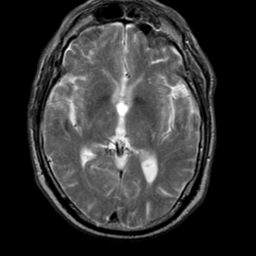

Meningioma, MR Study #2 -- Slice #9

[Home][Help][Clinical] Slice 9